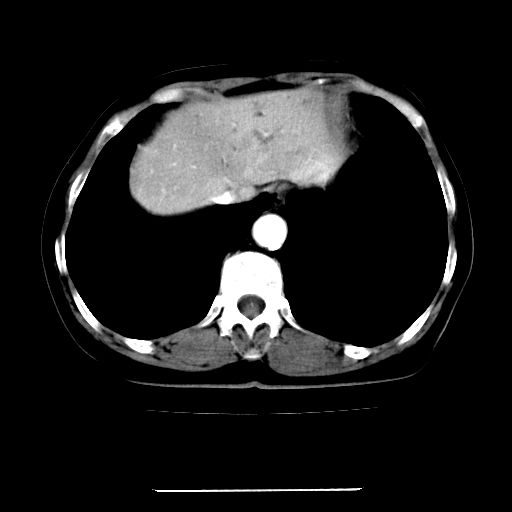

标题: CT22301:女,67岁,上腹部疼痛一周伴皮肤黄染,无发热。 [打印本页]

女,67岁,上腹部疼痛一周伴皮肤黄染,无发热。

左叶肝内胆管结石,并远端肝内胆管扩张。

考虑:肝内胆管结石继发肝内胆管扩张,右肾旋转不良。

支持肝内胆管结石并肝内胆管扩张。

肝内外胆管结石并肝内胆管扩张。

建议薄层观察,除外肝门部胆管细胞癌

考虑肝胆管癌;胰头占位?【形态失常,体积增大】

1、肝门高密度影下层面和胰头层面可见轻度胆管扩张,而静脉和延迟期均未见扫描完胰头,不能完全排除胰头占位。2、肝门部高密度影,考虑钙化或结石。

考虑肝门胆管癌伴门脉左支受侵包埋,建议mrcp进一步检查。